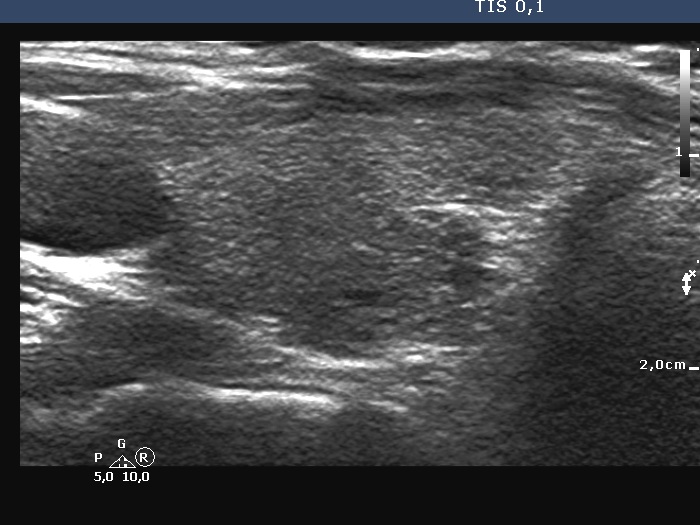

Ultrasonography. The thyroid was echonormal and had some minimally hypoechoic areas. A thick connective tissue band crossed the right lobe. Dorsal to this fragment the thyroid was very hypoechoic. On transverse scan, this area seemed to be a nodule. However, analysis of multiple sections revealed that this area was not a true nodule.

The longitudinal scanning is almost always more important than the transverse investigation, because larger parts of the thyroid are visualized in the former.